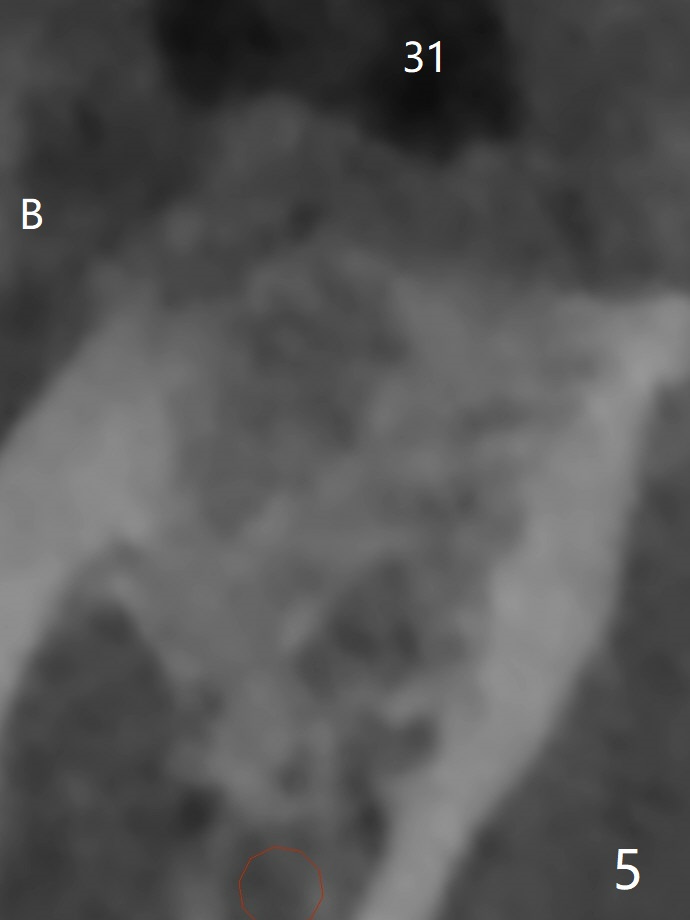

Bone Density Post Extraction with or without Bone Graft

Edentulous Lower Molar